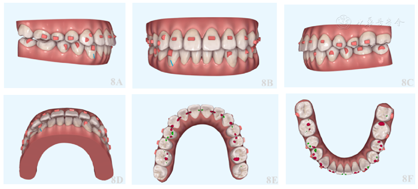

矫治方案设计33-43各牙近远中邻面片切0.25 mm,关闭前牙散在间隙,达到前牙正常覆合覆盖,双侧后牙重咬合(图8)。

该患者矫治时间共29个月,矫治后患者自然状态下左右面部基本对称,颏部无明显偏斜,面下1/3高度减小,相貌趋向直面型,颏部肌肉放松。口内检查显示,前牙达到正常覆合覆盖,双侧尖磨牙I类咬合关系,上下中线齐,上下牙弓均呈光滑卵圆形,患者具有前牙和尖牙保护合。曲面断层X线片显示矫治后各牙牙根平行度尚可,未见明显牙根及牙槽骨吸收。CBCT显示左侧关节间隙减小,双侧髁突骨皮质连续;各牙根尖均位于松质骨内。矫治后头颅侧位X线片显示:SNA角80.5°,SNB角78.6°,ANB角1.9°,FH-MP角35.0°,PP-GoGn角29.4°,矫治后FH-MP角较术前减小1.9°。矫治前后头颅侧位片X线片重叠图显示下颌稍有逆时针旋转。术后2年随访记录显示患者面部无明显偏斜,咬合关系良好,双侧髁突骨皮质连续光滑,牙齿根骨关系正常,治疗效果稳定(图9,图10,图11,图12,图13,表1)。